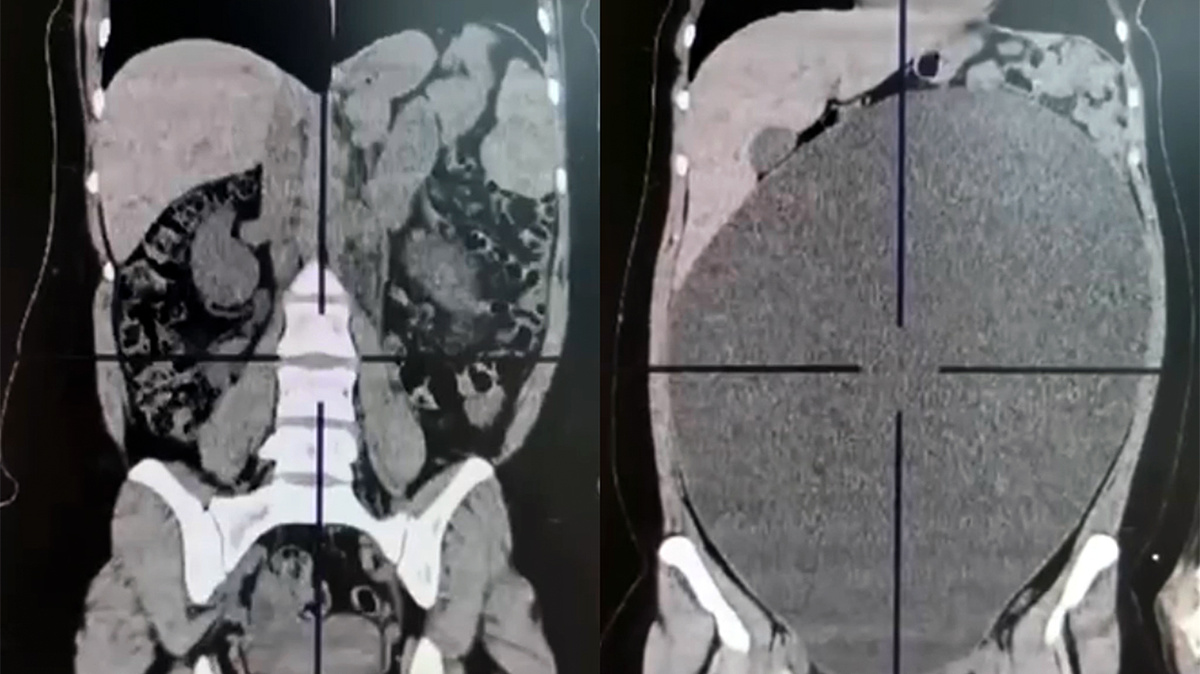

В московскую Городскую клиническую больницу №15 им. О.М. Филатова обратилась 20-летняя девушка с жалобами на боль, вздутие, увеличение объема живота и отсутствие стула. Пациентке провели компьютерную томографию с контрастированием, которая выявила образование яичника диаметром почти 40 см.

Лапароскопическим методом через несколько небольших проколов врачи гинекологического отделения смогли удалить объемное образование, сохранив яичник. Благодаря органосохраняющей операции молодая девушка сможет стать мамой в будущем.